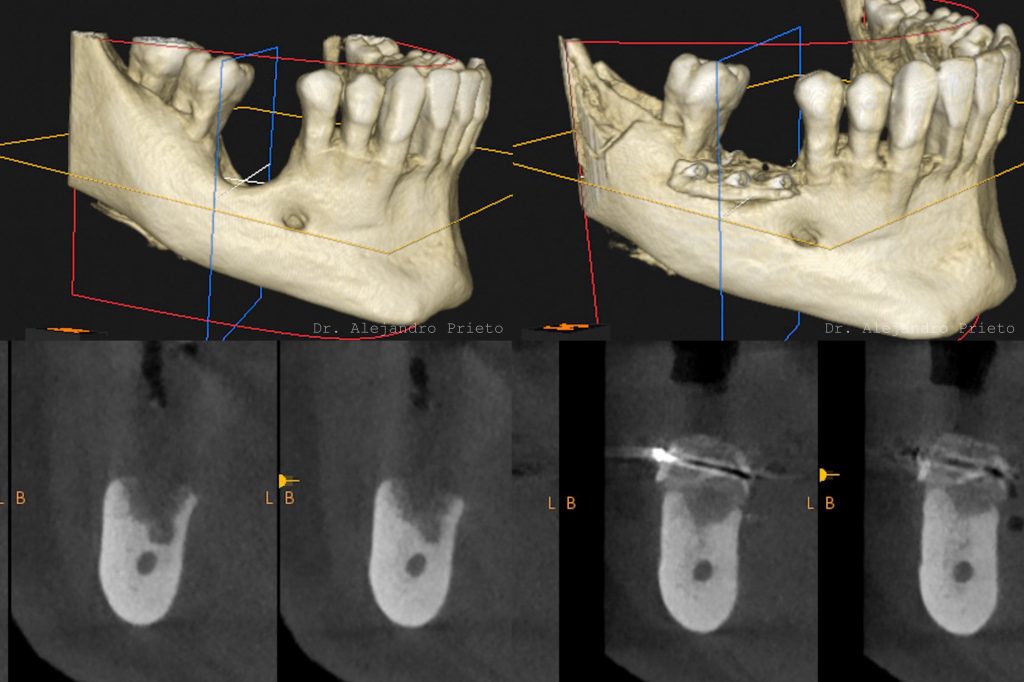

Injerto de hueso dental

Un injerto de hueso dental es un procedimiento quirúrgico que estimula la regeneración de la masa ósea que da soporte al implante. Se hace por medio de materiales biológicos o sintéticos.

¿Qué es el injerto de hueso dental?

Un injerto de hueso dental es una técnica quirúrgica que permite aumentar la masa ósea en el maxilar o la mandíbula.

Mediante la implantación de material de injerto se promueve la regeneración de las células óseas con el fin de aumentar su volumen y restaurar tanto su capacidad de soporte como su estética.

Este tratamiento puede tener diferentes finalidades. La más habitual es proporcionar el soporte necesario para la colocación de implantes.